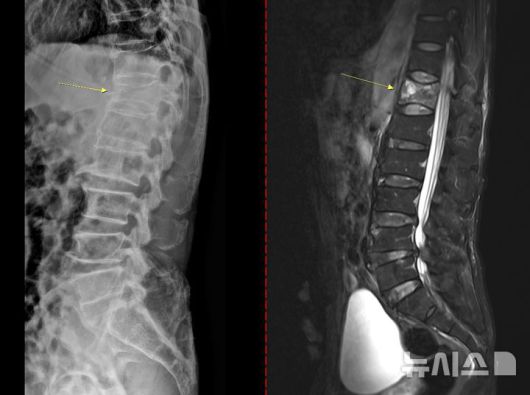

[서울=뉴시스] 골다공증성 압박골절 환자의 척추 엑스레이(왼쪽) 와 MRI(오른쪽). (사진= 고려대안산병원 제공) |

골다공증은 초기 징후가 뚜렷하지 않아 특히 주의해야 한다. 통증이나 자각 증상이 거의 없다가 시간이 지나 가벼운 충격만으로도 손목이나 대퇴골(엉덩이뼈)이 골절되면서 뒤늦게 진단되는 경우도 있다. 때로는 등이 굽거나 키가 줄어드는 척추 압박골절이 나타날 수도 있다. 심할 경우 허리를 구부리거나 기침을 하는 등 일상생활 중에도 뼈가 쉽게 부러질 수 있다.

치료 없이 방치하면 뼈는 점점 약해지고 척추와 손목, 대퇴골 골절 등 중대한 골절이 발생할 수 있다. 특히 대퇴골 골절은 고령 환자에서 수술 후 합병증, 장기 입원, 사망률 증가와 직결되는 중증질환이다. 척추 압박골절의 경우 자세 변화, 만성 통증, 보행 장애를 유발해 ▲활동량 감소 ▲근력 저하 ▲추가 골절의 악순환으로 이어진다.